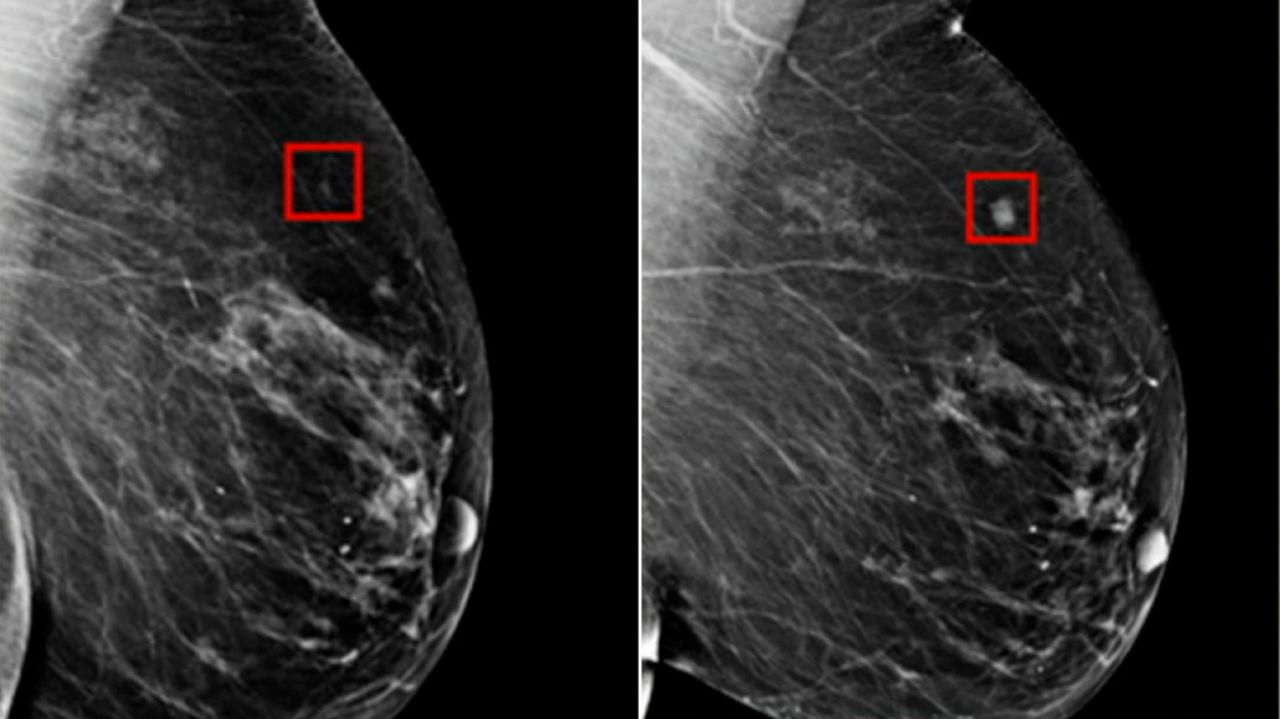

In a completely different domain, Mixture of Modality Experts (MOME) refers to a groundbreaking AI model developed by the Hong Kong University of Science and Technology (HKUST) for non-invasive breast cancer diagnosis.

This model leverages a mixture-of-experts framework and transformer architecture to effectively fuse information from multiple imaging modalities, specifically multiparametric MRI (mpMRI), achieving expert-level accuracy comparable to experienced radiologists.

This MOME model is entirely distinct and unrelated to the Mixture of Matryoshka Experts framework developed in collaboration with Meta AI. They are separate research initiatives with different goals, developers, and underlying technologies.

China's largest mpMRI breast cancer dataset for training and validation Transformer-based MoE framework for multimodal fusion Multi-institutional partnership including medical institutions